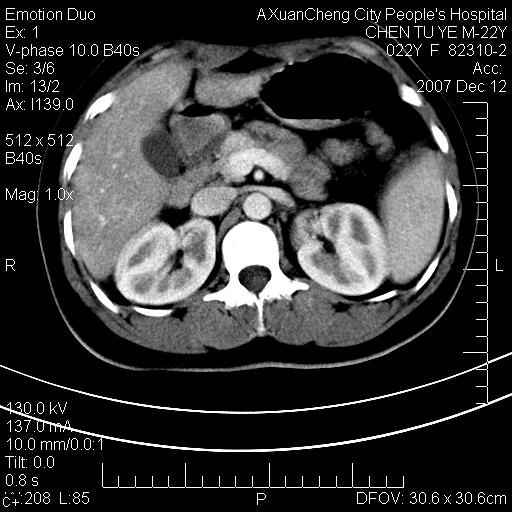

1 脾大,慢性肝损伤. 2 肝脏脂肪侵润.  3 你所指的部位疑点,我没看出有问题.

1 脾大,慢性肝损伤. 2 肝脏脂肪侵润.

脂肪肝,脾大

重度脂肪肝.